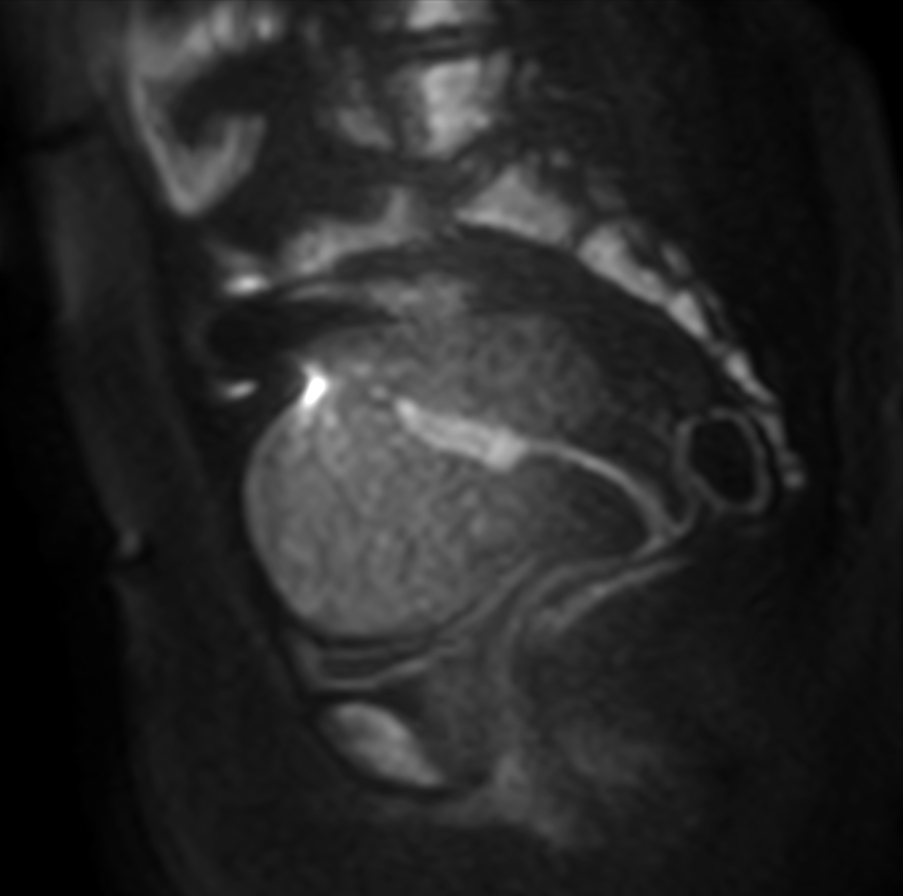

Sagittal T2w SSh